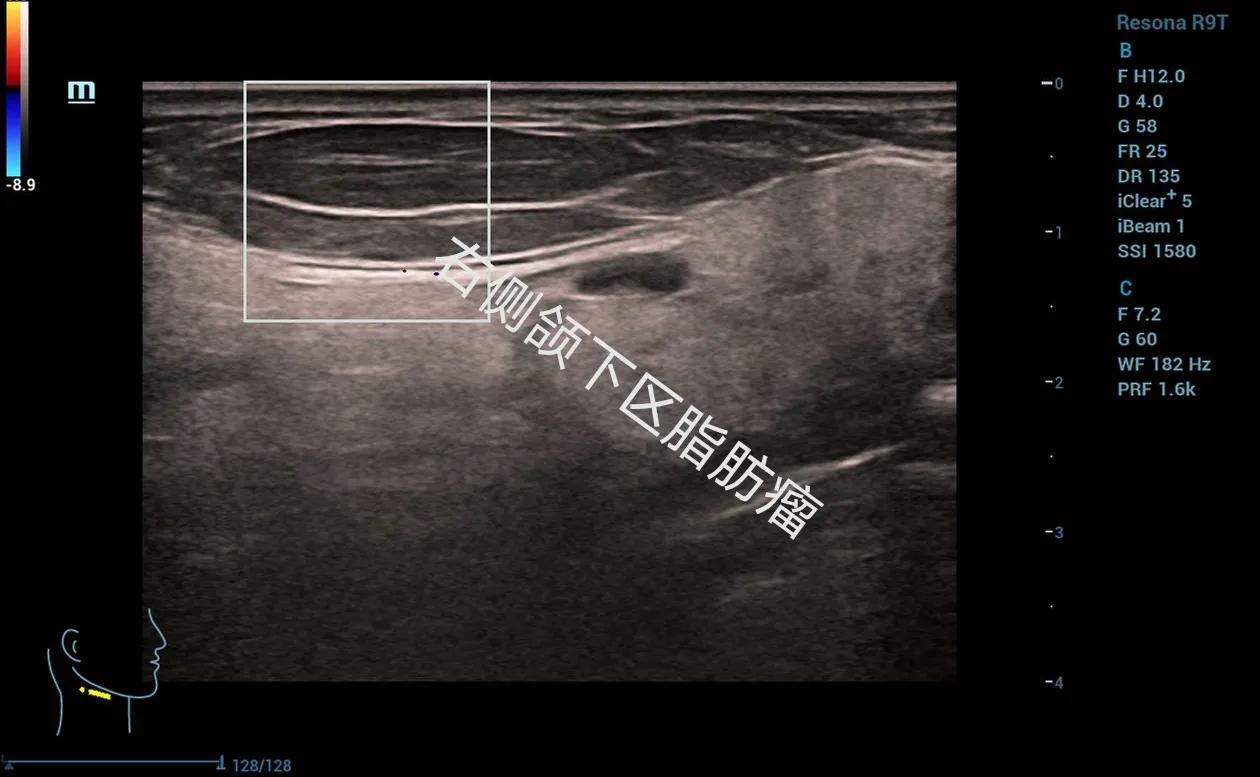

下面给大家分享几个我平时做的病例,发生在各个部位的脂肪瘤。

低回声的脂肪瘤,内部可见高回声的纤维分隔,可见少量血流信号